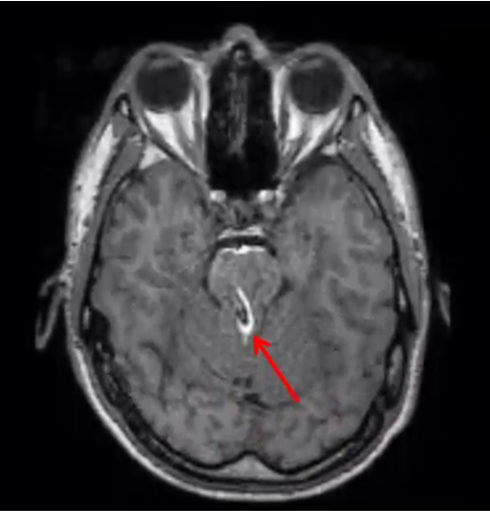

k-space data error (herringbone)

A single erroneous data point (spike) in k-space creates a line pattern through the image

if data point is on the x-axis the lines will be verticle, if the data point error is on the y-axis the lines will be horizontal. If the lines are diagonal, the data error is not on an axis.

how to fix: Repeat the scan without parameter changes (usually due to random error). But, if it occurs frequently as faulty coil may be the problem